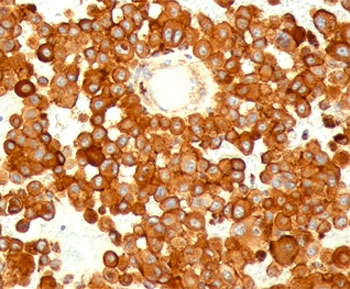

CD63 Antibody / LAMP-3 [orb2637613]

FACS, IF, IHC-P, WB

Human, Mouse

Mouse

Monoclonal

Unconjugated

100 μg